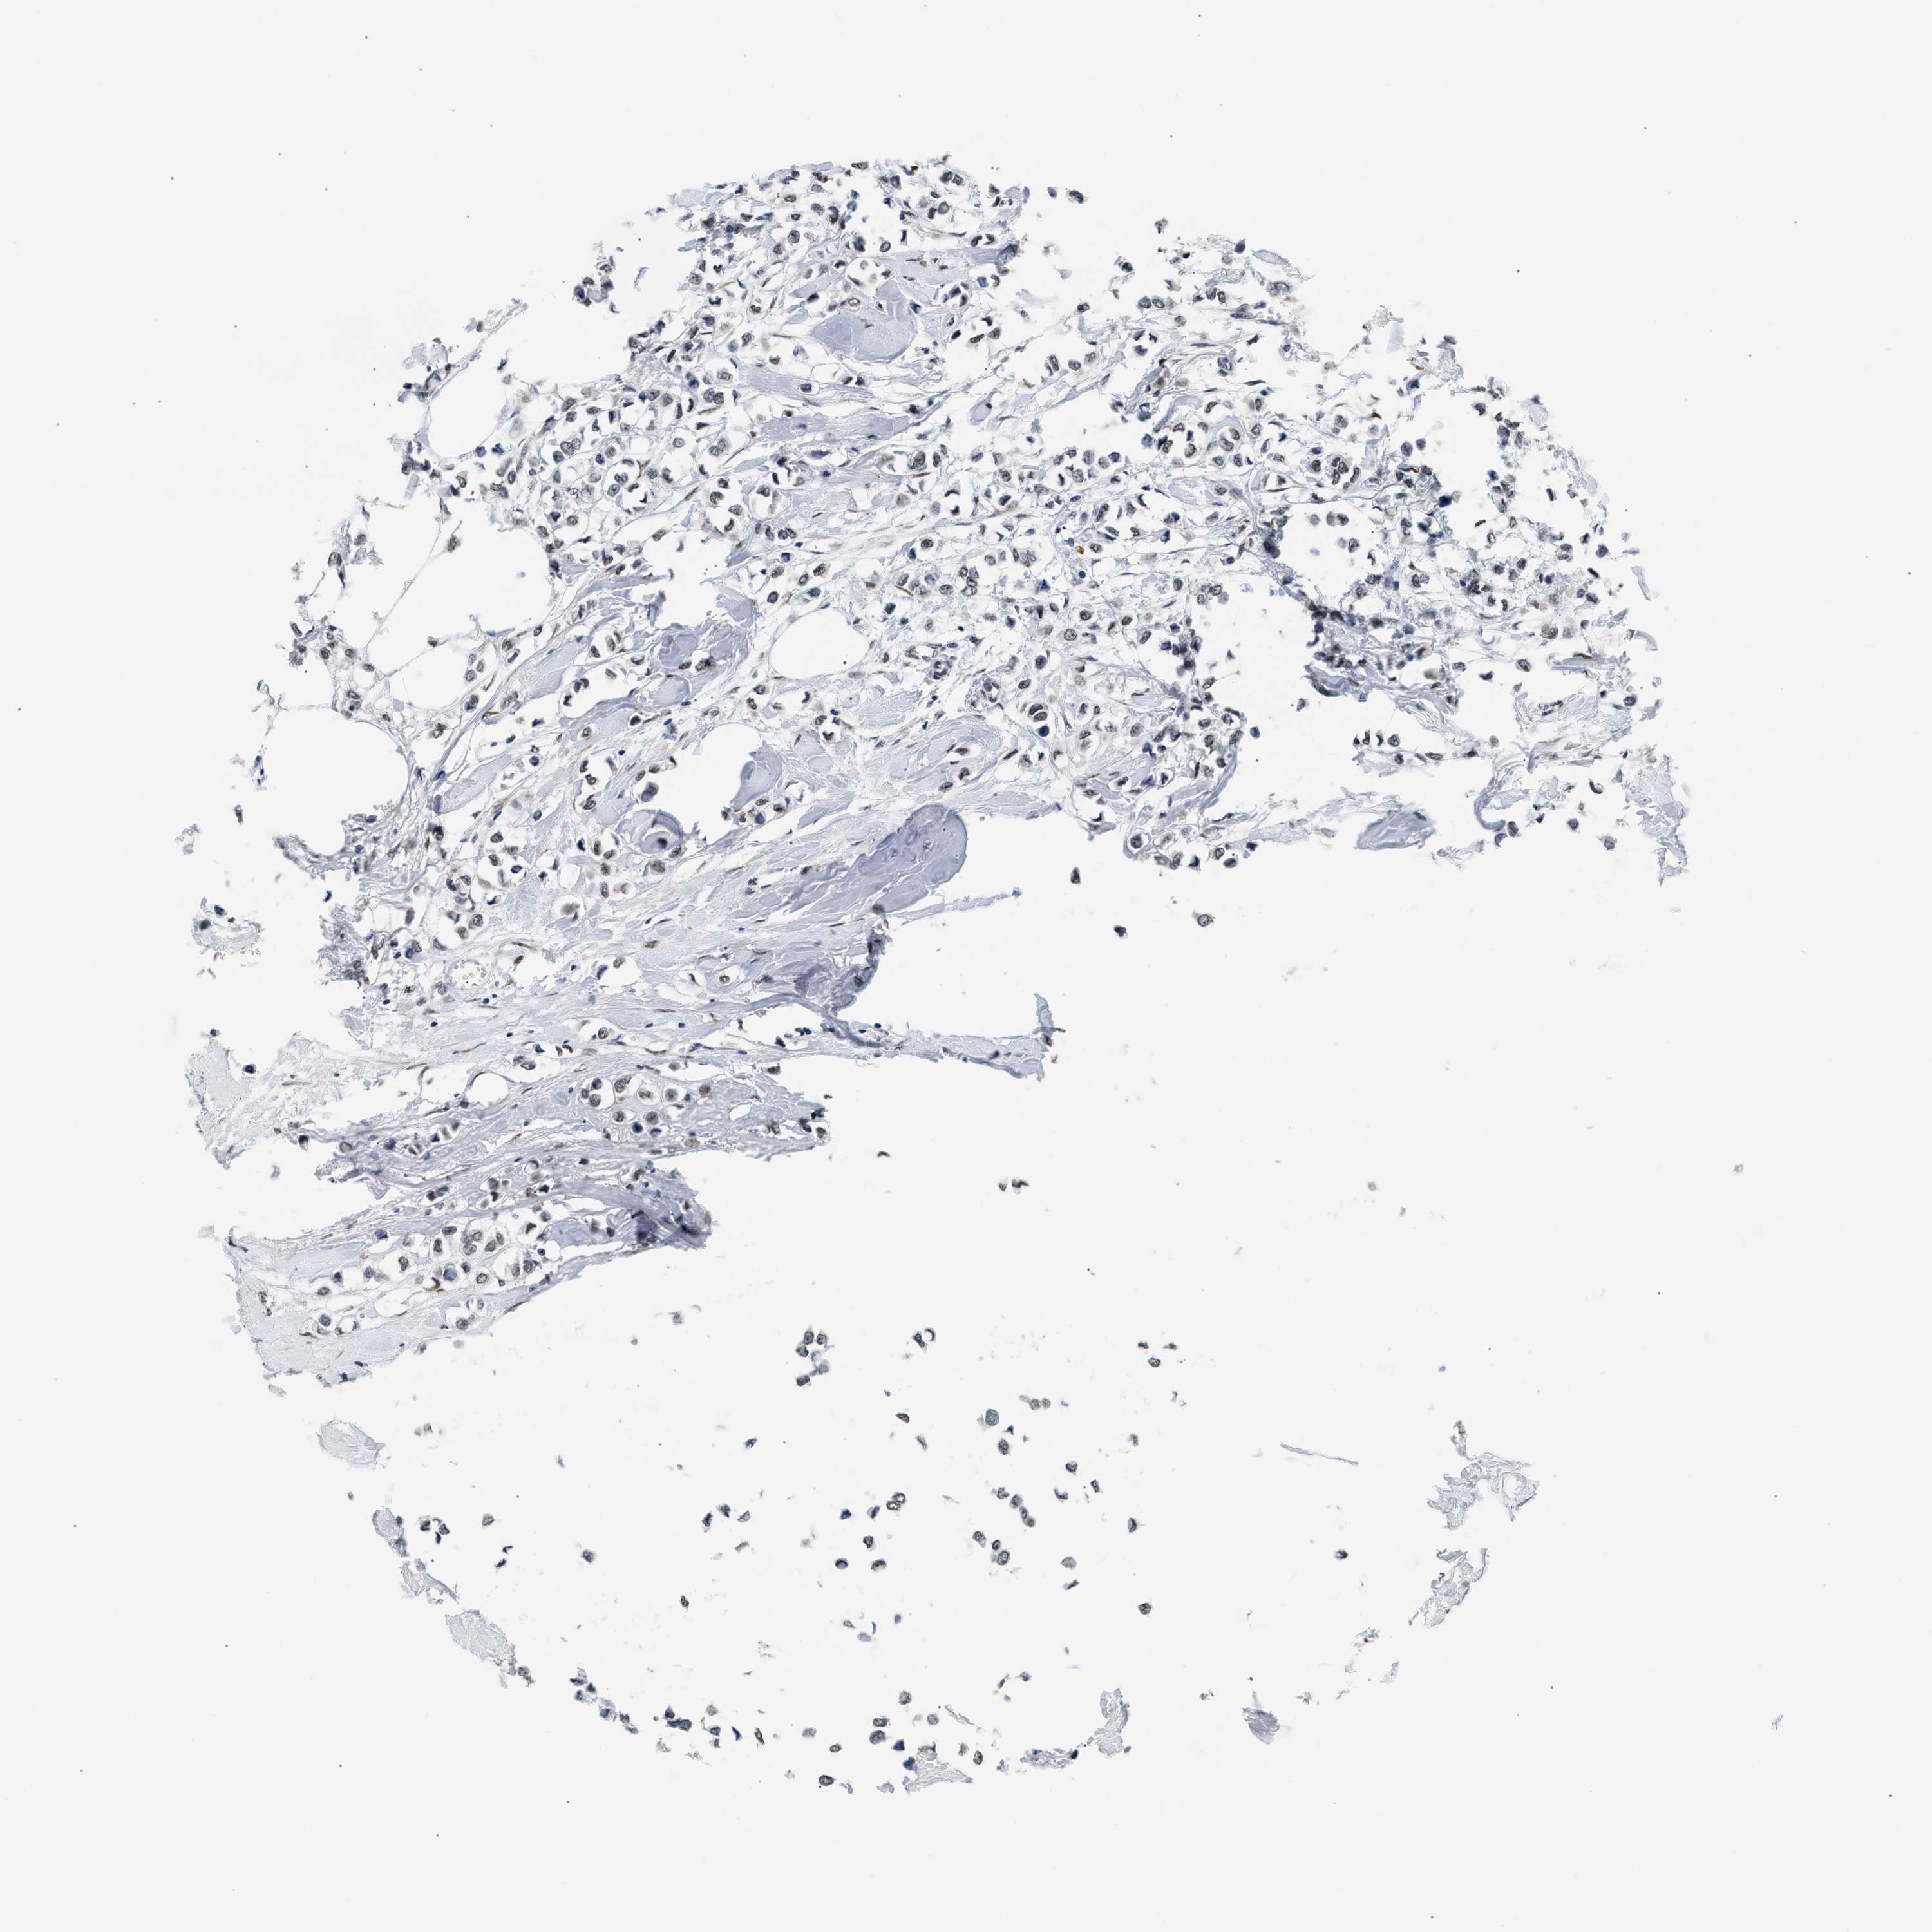

CANCER BREAST CANCER Show tissue menu

BRCA TCGA BRCA VALIDATION PROTEIN EXPRESSION